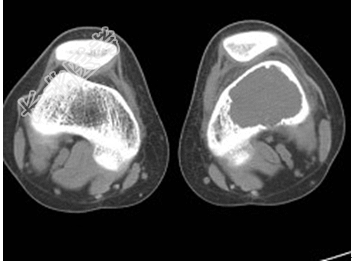

- [材料题] 患者,男,33岁,左股骨肿块半年余,无明显症状,查体一般情况良好。

- 简答题1、结合所提供的图像,该患者诊断为?

- 1、该患者诊断是?2、该疾病的治疗原则是